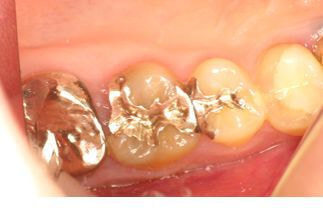

根管治療後の痛みの原因は、実は治療している歯でない場合や不適切な根管治療によって起こる場合、急性の歯髄炎によるものや急性根尖性歯周炎によるものなど様々です。

抜歯を勧められた場合でも、実は根管治療時の感染のコントロールが不十分なことが原因で治っていないケースが結構あり、そのような場合は根管治療で残すことが出来ます。